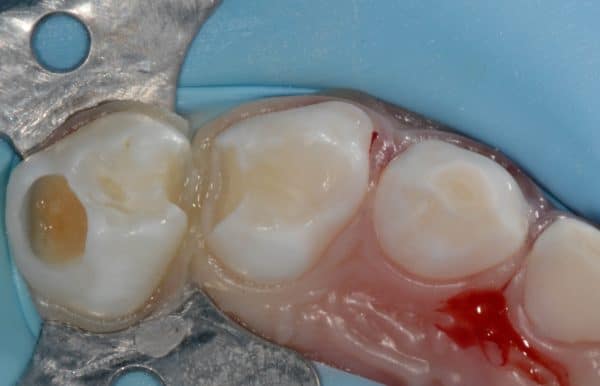

Caries dentaires affectant deux molaires de lait. Un champ d’isolation empêche la contamination des surfaces dentaires traitées, évite les accidents dentaires et réduit le contact de matériels avec la bouche de l’enfant.

Les différentes étapes pour soigner une carie sur une molaire de lait sont illustrées, depuis l’ouverture de la cavité carieuse, le nettoyage du tissu malade et la restauration de la dent avec du composite.